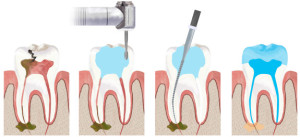

Pasi eshte bere anestezia,pastrimi i mases karioze ne kurore,hapet dhoma pulpare (nese nuk eshte hap nga prishja ) dhe pas heqjes se pulpes koronare fillohet me trajtimin endodontik te kanaleve.Nuk perjashtohen rastet kur anatomia e dhembit varion nga ajo normale,por dhembet ne te dy nofullat kane si me poshte:

Perpunimi kimik dhe fizik i kanaleve ,behet me instrumenta te posacem dhe me materiale te ndryshme ne varesi te patologjise se nervit te dhembit .Zakonisht dhembet qe i nenshtrohen trajtimit endodontik ,kerkojne me shume se nje seance per tu trajtuar.Vetem atehere kur mjeku eshte i bindur se perpunim i kanalit eshte kryer sic duhet,nuk ka me mbetje apo mikroorganizma ne kanal apo perreth rrenjes ,pacienti nuk ka me

Perpunimi kimik dhe fizik i kanaleve ,behet me instrumenta te posacem dhe me materiale te ndryshme ne varesi te patologjise se nervit te dhembit .Zakonisht dhembet qe i nenshtrohen trajtimit endodontik ,kerkojne me shume se nje seance per tu trajtuar.Vetem atehere kur mjeku eshte i bindur se perpunim i kanalit eshte kryer sic duhet,nuk ka me mbetje apo mikroorganizma ne kanal apo perreth rrenjes ,pacienti nuk ka me  dhimbje,dhe ne grafi kontrolli shikohet eleminimi i proceseve periapikale,atehere kanali eshte gati per tu mbushur.Ne kliniken tone perdoren materiale te firmes

dhimbje,dhe ne grafi kontrolli shikohet eleminimi i proceseve periapikale,atehere kanali eshte gati per tu mbushur.Ne kliniken tone perdoren materiale te firmes